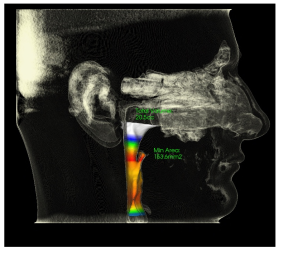

- Airway MCA: 153.6mm2 (at risk for OSA less than 150mm2)

CBCT - airway